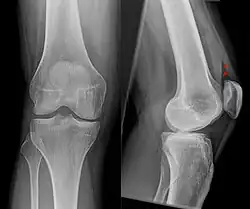

Als Okkulte Fraktur bezeichnet man einen Knochenbruch (Fraktur), der in der normalen Röntgenaufnahme nicht erkennbar oder nicht direkt erkennbar ist. In einigen Fällen können indirekte Frakturzeichen auf das Vorhandensein einer Fraktur hinweisen, in anderen Fällen ist allein anhand des Röntgenbildes der Bruch überhaupt nicht erkennbar. Bei entsprechendem Verdacht – zum Beispiel aufgrund von heftigen Schmerzen – kann dann in den meisten Fällen eine Magnetresonanztomographie (MRT) oder eine Computertomographie (CT) den Bruch zeigen oder ausschließen. Bei Patienten, für die z. B. wegen eines Herzschrittmachers eine MRT nicht in Frage kommt, kann auch eine Skelettszintigraphie zum Frakturnachweis durchgeführt werden.

Auch in nach Tagen bis Wochen angefertigten Röntgenaufnahmen kann eine zunächst okkulte Fraktur sichtbar werden. Es zeigen sich dann die Reaktionen des Körpers auf den Knochenbruch wie Verminderung der Knochendichte am Bruchspalt durch Resorption oder Verdickungen oder Verkalkungen der Knochenhaut im Rahmen der Knochenbruchheilung. Im ungünstigeren Fall kommt es doch noch zu einer Verschiebung der Knochenbruchstücke gegeneinander, so dass der Frakturspalt direkt sichtbar wird.